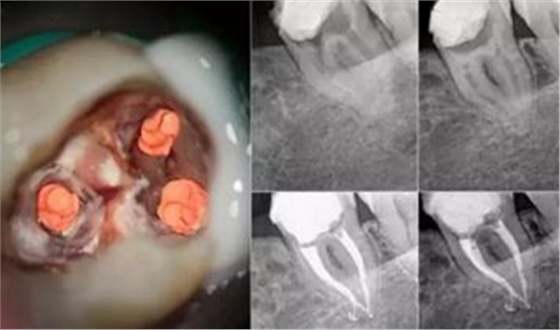

另外針對于磨牙來講,通常磨牙會有3到4個牙根,但是牙根里面的神經(jīng)可能會有多根,正常的磨牙根管治療是指治療3根神經(jīng)的費用,如果這個牙齒的神經(jīng)數(shù)量超過3根那么每多出來一根就要加收一根神經(jīng)的費用。

出現(xiàn)這種情況,可能是醫(yī)生沒有將牙髓清理干凈,導致發(fā)炎感染,這時候就得將填充材料取出,重新再做一次根管治療。記得最后要套上一顆烤瓷牙冠保護原牙,因為牙齒失去牙髓唯一的營養(yǎng)來源,變得又黑又脆弱,跟死牙沒什么區(qū)別,吃東西容易崩壞。所以找個靠譜的牙醫(yī)很重要哦,為了避免二次根管,一定要擦亮眼睛,選一位好牙醫(yī)呢!